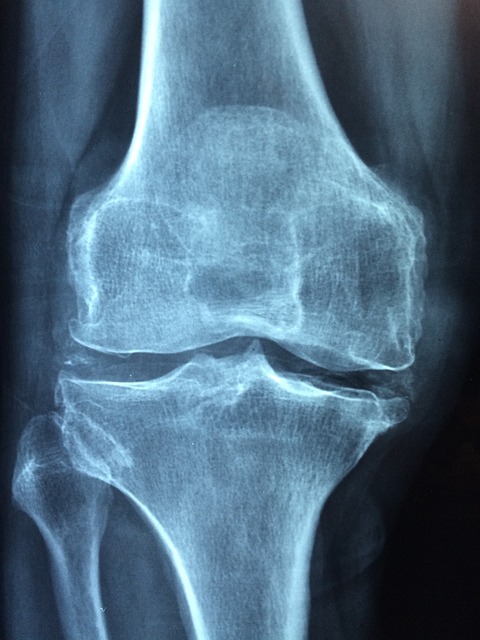

MBP(Milk Basic Protein)는 우유에서 극소량 추출되는 고기능 단백질로, 식약처에서 골밀도 유지 기능성을 인정받은 성분입니다. MBP는 뼈의 세포 활동 자체에 영향을 주는 기능성 원료라는 점에서 칼슘제와는 차별화됩니다.

- 조골세포(뼈 생성 세포)를 활성화하여 새로운 뼈가 형성되도록 돕고

- 파골세포(뼈 파괴 세포)의 활동을 억제하여 뼈 손실을 줄여줍니다